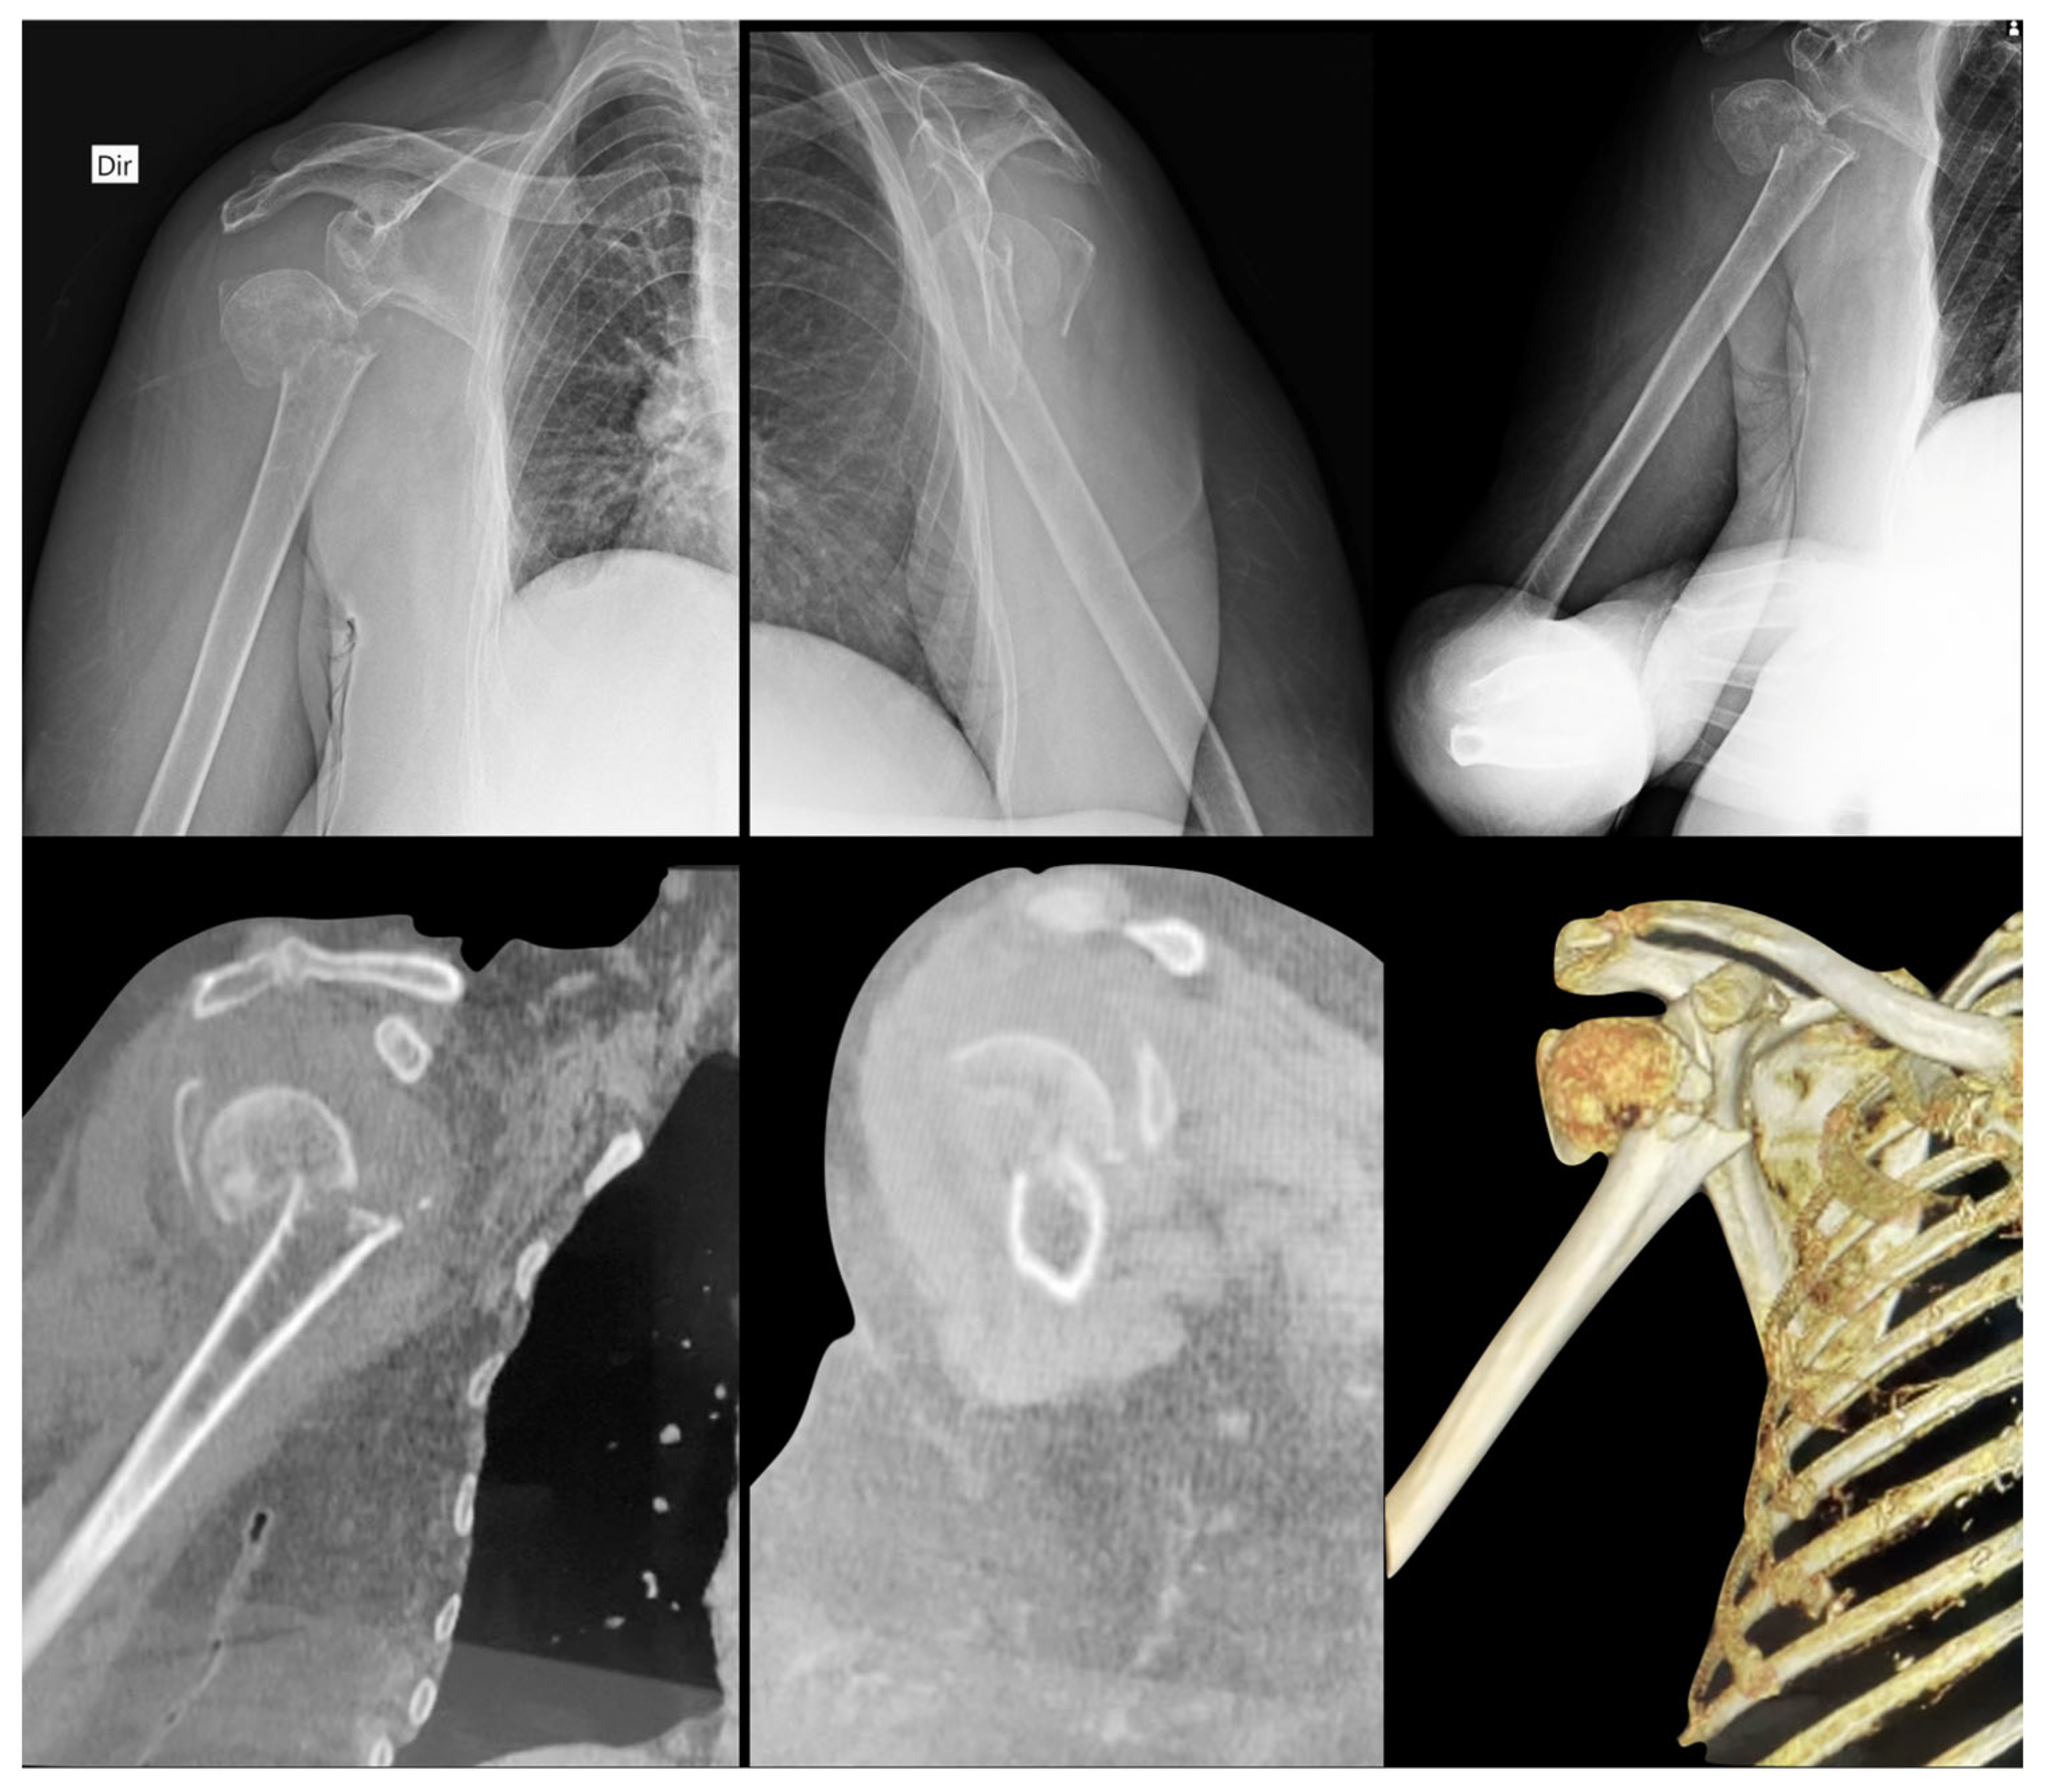

- We separated 20 cases of fractures of the proximal humerus, with X-rays and CT images, individualized in a separate folder;

- We ask that each examiner define which Hertel criteria are present by evaluating the radiographs and then their respective CT scans;

- In the folder with the files there is a photo explaining each of the 3 Hertel criteria, (reproduced from these author original article);